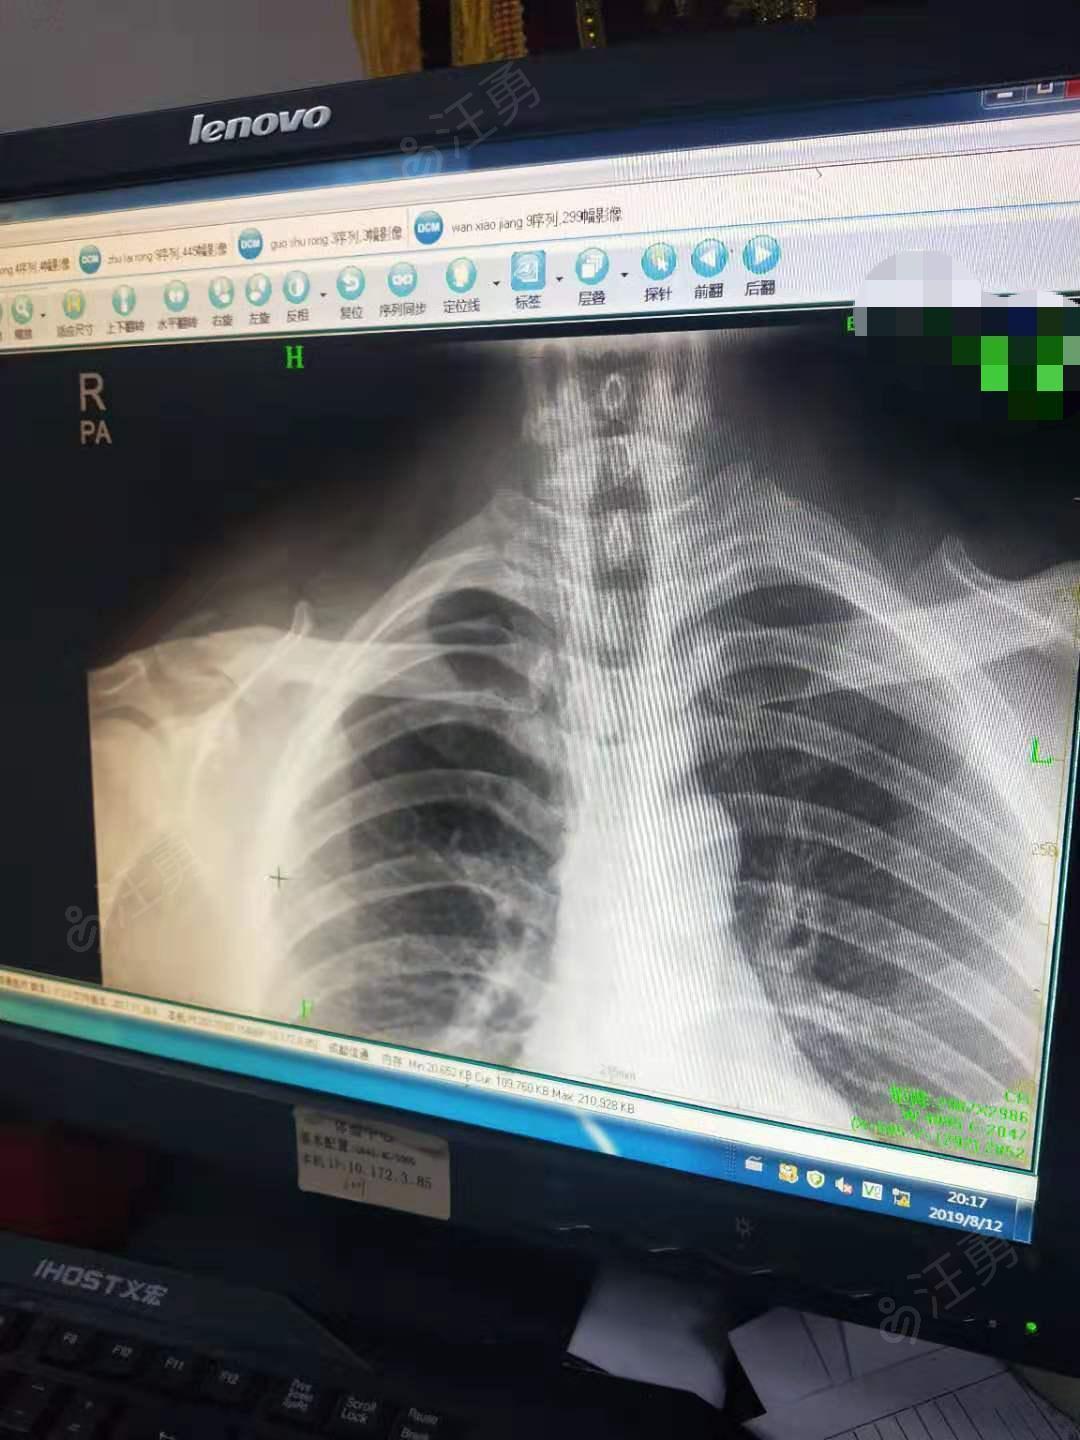

儿童锁骨青枝骨折图片

儿童锁骨青枝骨折图片,儿童青枝骨折图片

骨科医院来看看我这个锁骨远端骨折内固定术前和术后一个月的片子